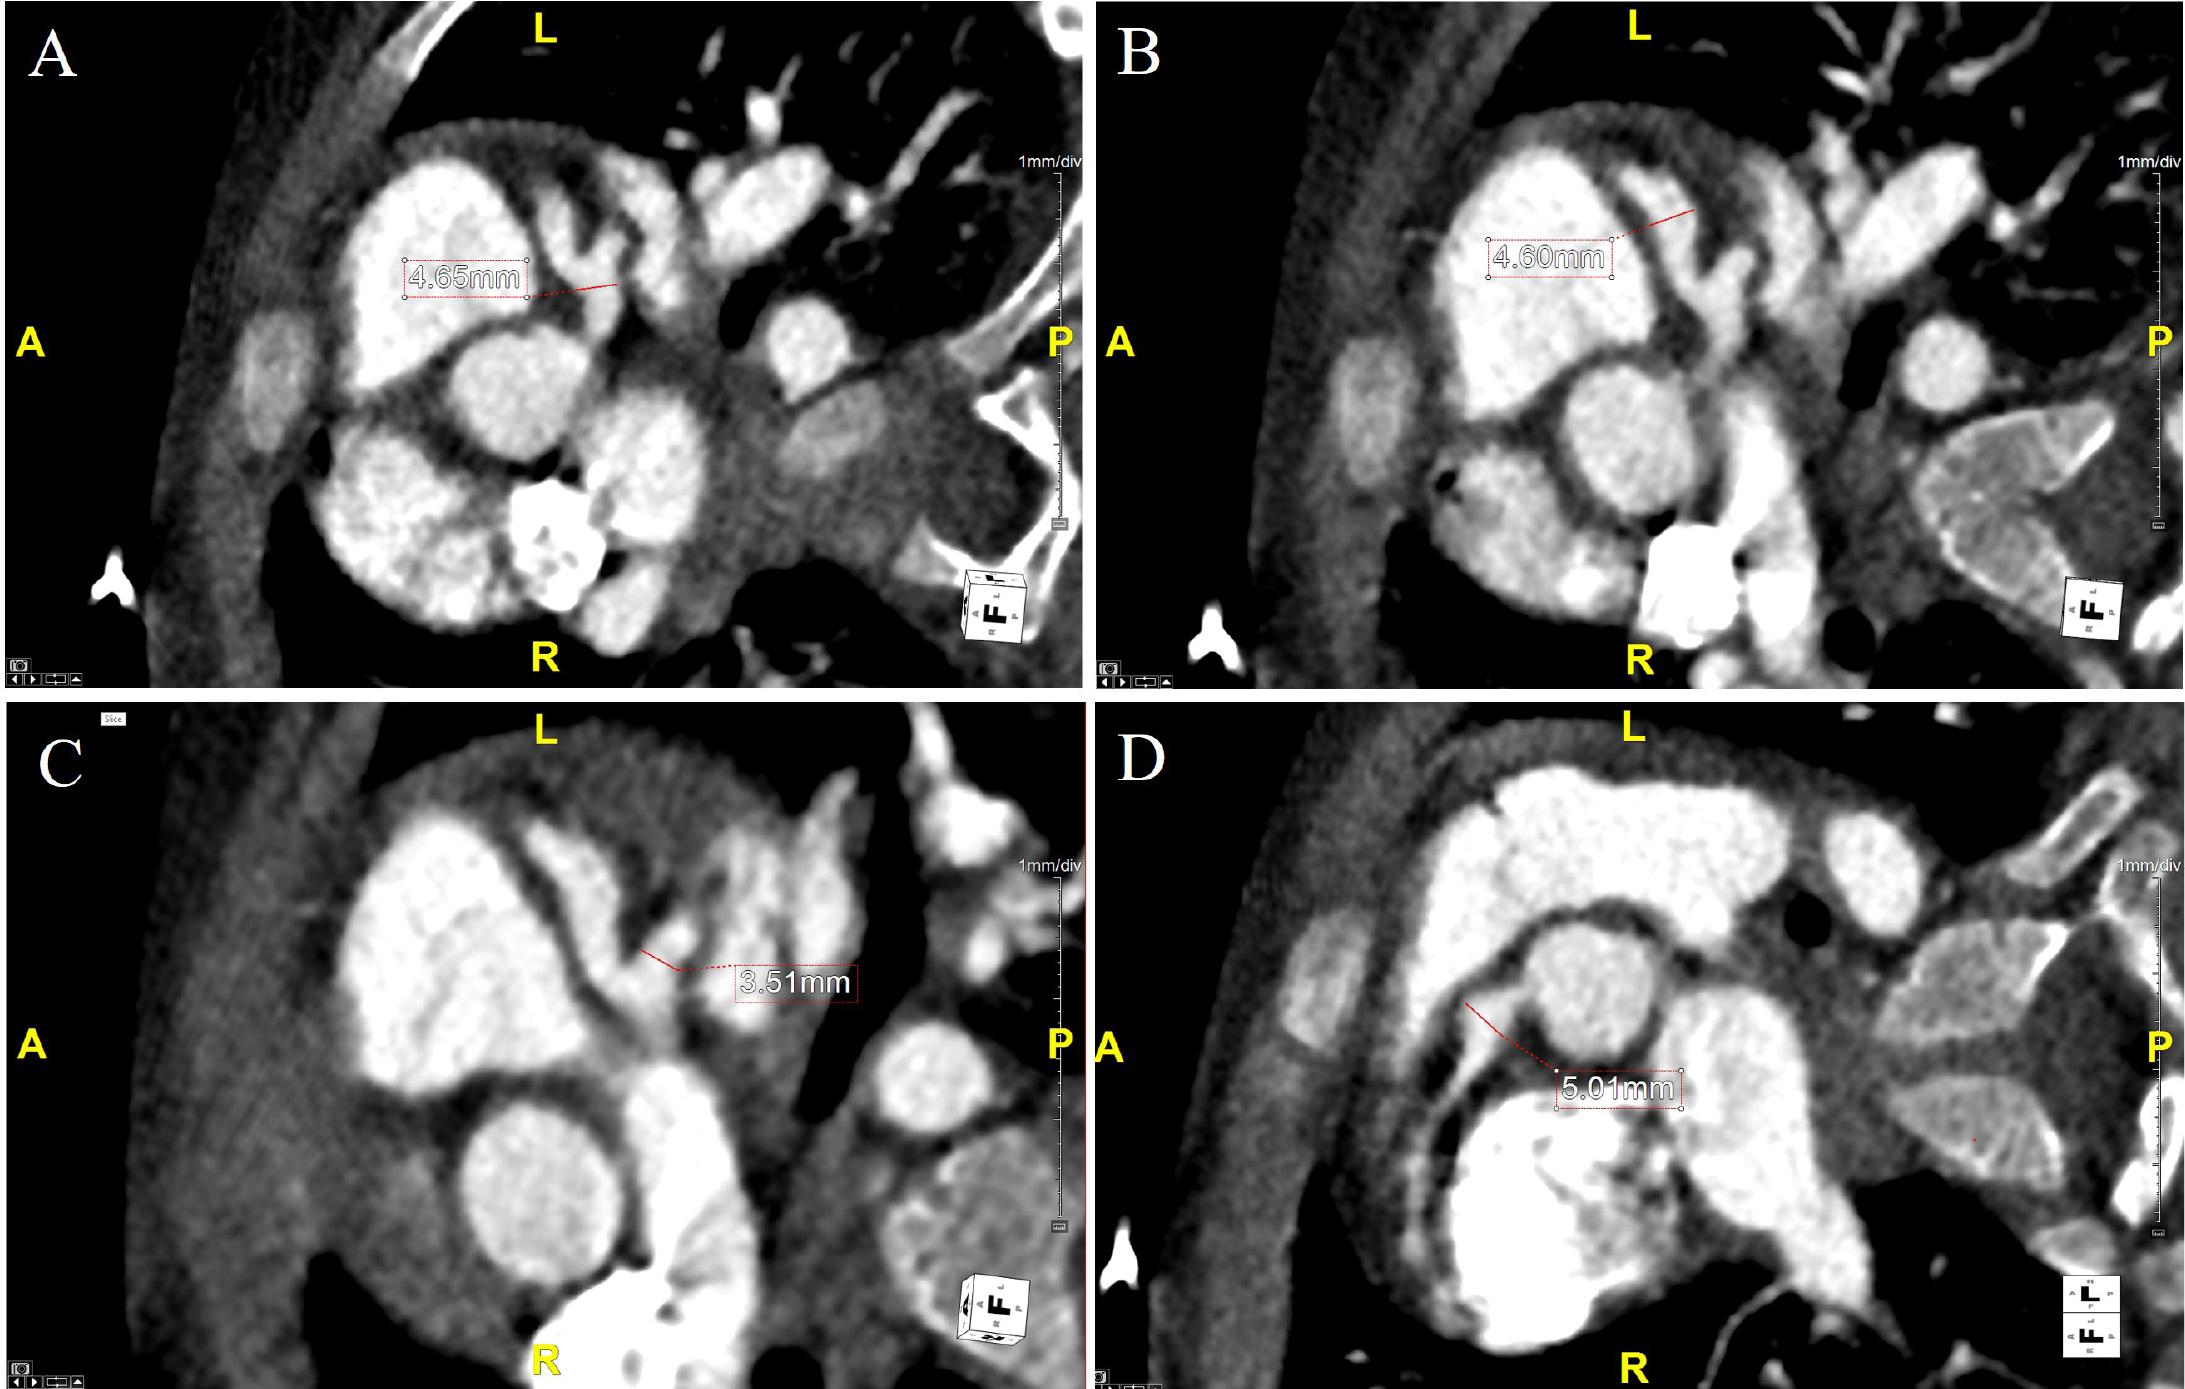

On arrival, ECG demonstrated sinus tachycardia with a normal repolarization pattern (Figure 1). The TTE revealed a medium aneurysm of the RCA (Figure 2, Panel A-C), with a diameter of 5 mm (Z-score +7.8). The LMCA origin measured 3 mm (Z-score +1.6), and the proximal trunk of the LMCA (Figure 2, Panel D-E) measured 4 mm (Z-score +4.5). At the bifurcation of LMCA, a large aneurysm with a maximum diameter of approximately 8 mm (Z-score +10) was identified, with suspected thrombotic material observed within its lumen. The anterior descending artery (LAD) demonstrated a maximum diameter of 4 mm (Z-score +9). Given this suspicion of intracoronary thrombus, IV heparin was started, together with the overlapping of warfarin therapy until the INR was within the therapeutical range. Cardiac computed tomography (CCT) confirmed the coronary aneurysms, without evidence of intraluminal thrombi (Figure 3, Panel A-D).

Cardiac computed tomography showing axial plane after multiplanar reconstruction of the left main coronary artery (Panel A) with a maximum diameter of 4.6 mm (Z-score +5.3); the left anterior descending artery (Panel B) with a diameter of 4.6 mm (Z-score +10.0); the circumflex artery with a diameter of 3.5 mm; The right coronary artery in axial reconstruction (Panel D) depicts a proximal diameter of 5 mm (Z-score +9.0).